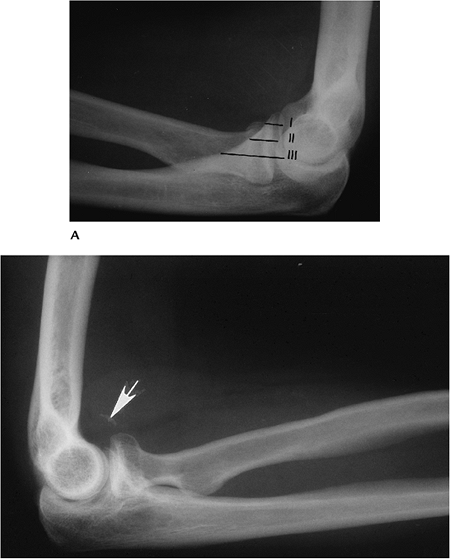

P.528

![]() |

FIGURE 8-12 (A)

Lateral radiograph demonstrating the locations of Types I to III coronoid fractures. Lateral radiograph of the elbow after reduction of a posterior dislocation shows a small fragment from the coronoid tip (arrow) (Type I). |